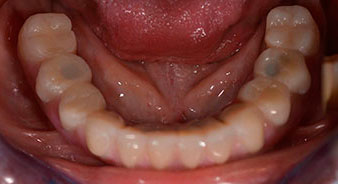

The impression and bite registration were then performed so that the dental technician could begin producing the provisional restoration immediately. This was then screwed in on the same day (Fig. 17 and 18).